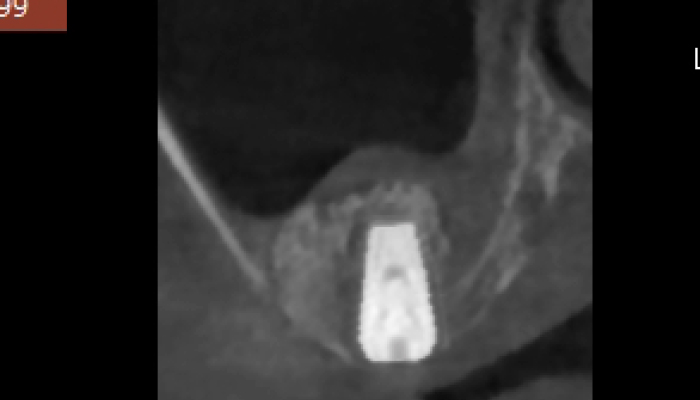

상악동거상술 수술사진

상악동거상술 전후 사례

• 식립 전

식립 후

• 식립전

식립후